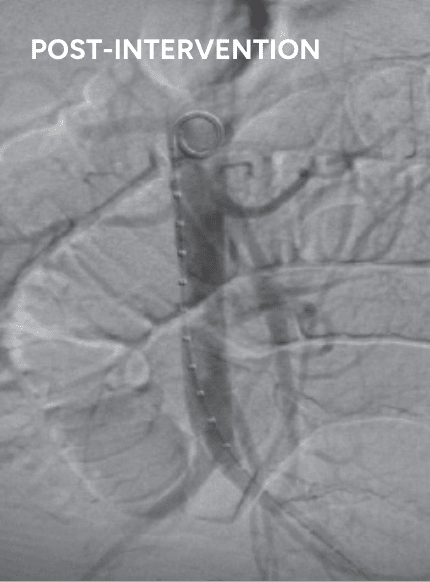

2.

venogram of occluded IVC filter

BASHIR™ Endovascular Catheter+40 total 25mg r-tPA